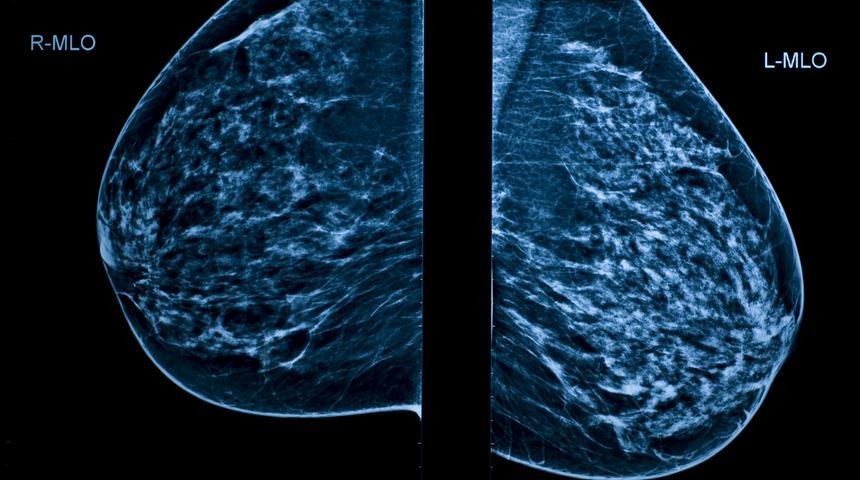

Kadınlarda meme sarkması yaşlanma, yer çekimi, hızlı kilo kayıpları, hamilelik ve emzirme gibi çok farklı durumlardan etkilenir. Mastopeksi ameliyatı ile fazla deri alınarak meme başı ve memeye ideal şekli verilir. Uygulanan farklı cerrahi teknikler olmakla birlikte amaç estetik olarak daha güzel görünen göğüslere kavuşmak olduğu için izler mümkün olduğunca sınırlandırılır.

Mastopeksi (meme dikleştirme) ameliyatı, tek başına ya da implant yerleştirilmesi ile birlikte uygulanabilir. Memeye implant uygulamaları meme büyüklüğünü artırmakla birlikte üst kısımda dolgunluk da sağlar. Meme dikleştirme ameliyatı hastanın sarkık olan meme yapısının toparlanmasında yardımcı olurken üst memede dolgunluk için protez kullanılması gerekmektedir. Ameliyat sırasında kullanılan dikişler eriyebilen dikişler olduğundan alınmasına gerek yoktur. Nadiren deri üzerine birkaç dikiş atılabilir ve bu dikişler bir hafta içinde alınır.